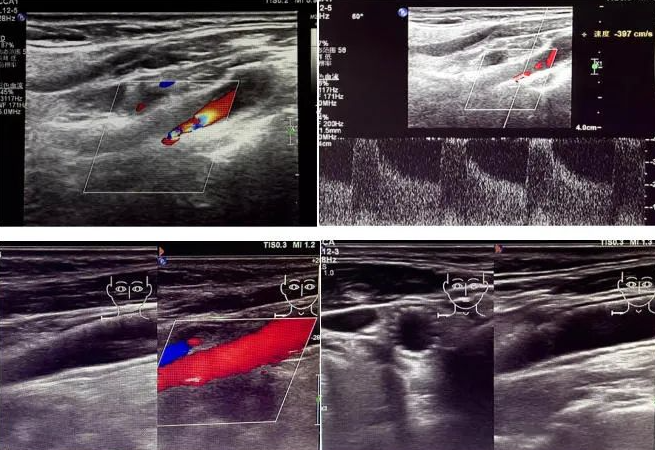

該患者因反復頭暈前來國文醫(yī)院就診。經(jīng)醫(yī)院超聲科運用高端超聲設備進行頸動脈超聲檢查后發(fā)現(xiàn),其右側頸動脈狹窄程度超過 90%。如此嚴重的狹窄狀況,猶如高速公路上的嚴重堵車,使得血液流通受阻,大大增加了腦梗死的風險,時刻威脅著患者的生命安全。

頸動脈超聲檢查作為一種無創(chuàng)、安全且準確的篩查手段,在評估血管健康狀況方面發(fā)揮著重要作用。它能夠清晰地顯示血管的狹窄程度以及斑塊性質,為臨床診療提供可靠的依據(jù)。國文醫(yī)院超聲科配備的高端超聲設備,更為精準診斷提供了有力支持。